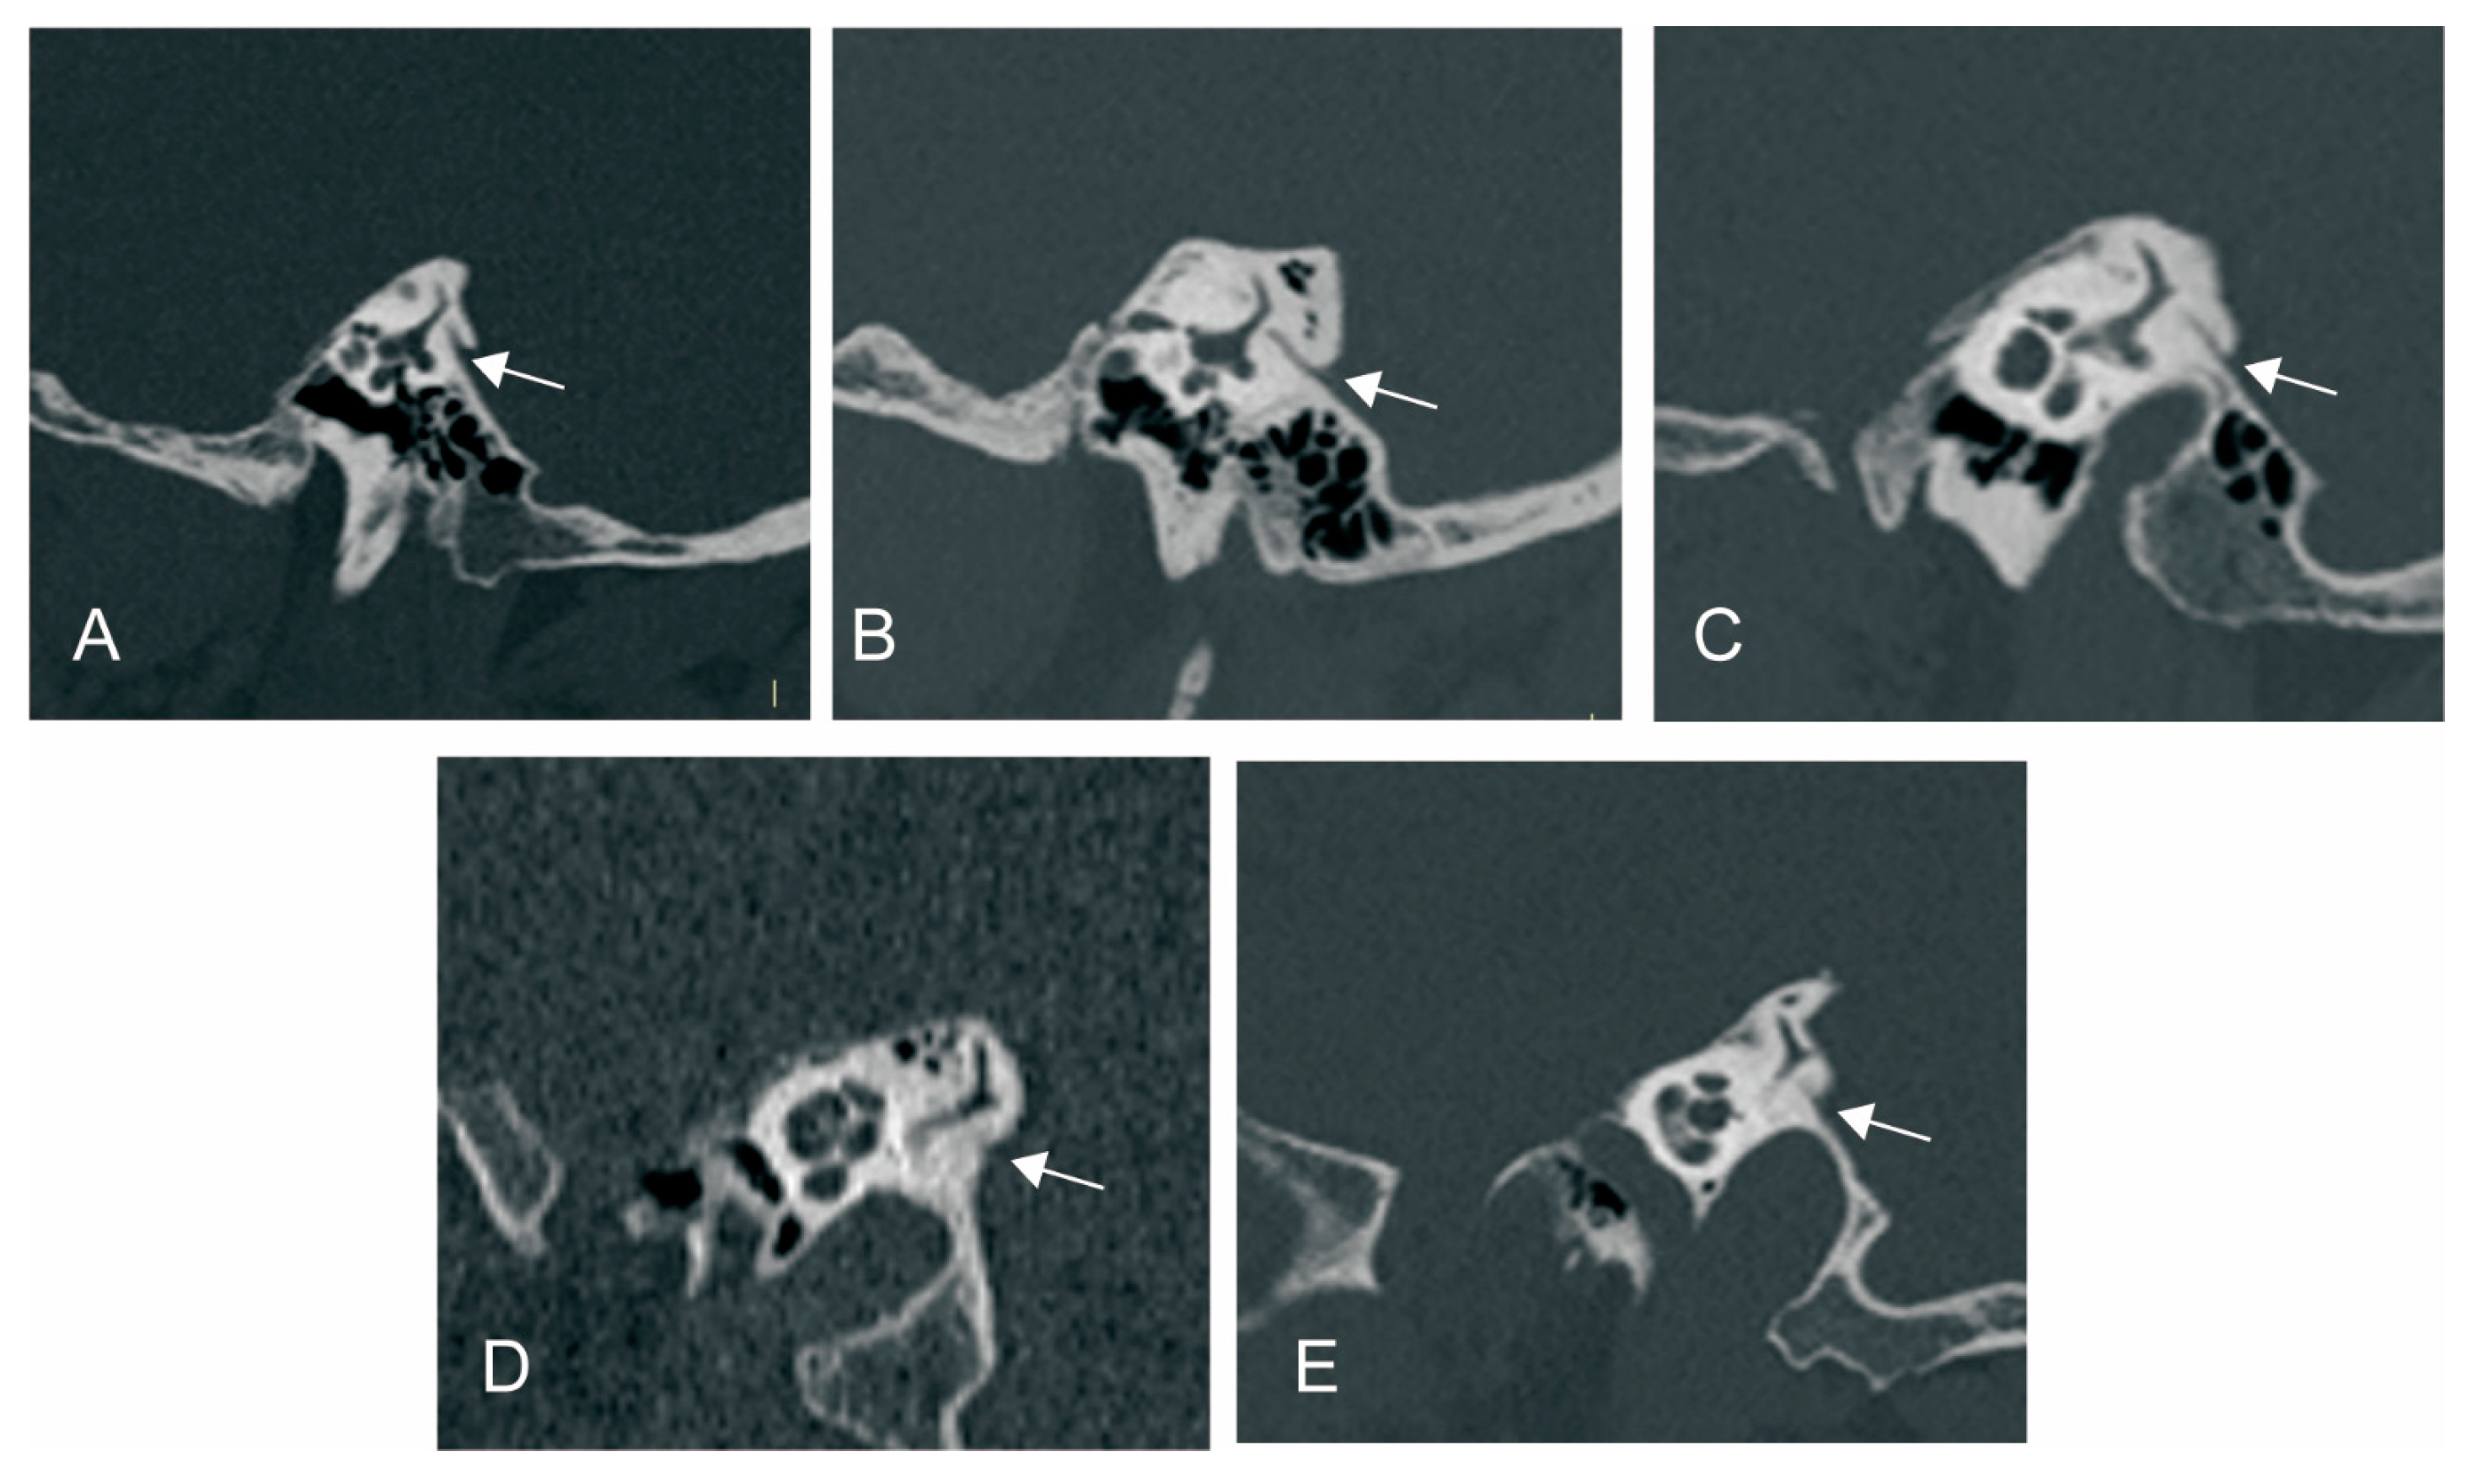

We used Yamane classification criteria to describe the morphology of VA [10]: (A) funnel type, (B) tubular type, (C) filiform type, (D) hollow type, (E) obliterated type (Figure 2).

Figure 2.

Vestibular aqueduct (VA) morphology subtypes. (A) Funnel type; (B) tubular type; (C) filiform type; (D) hollow type; (E) obliterated type. White arrow: VA.